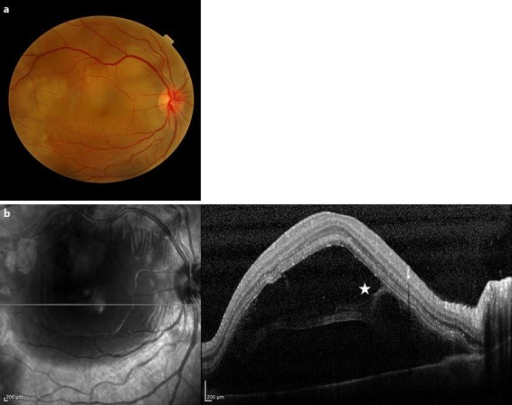

- Shifting fluid: 체위 변경에 따라 장액이 이동 (삼출성의 특징)

- 매끄러운 표면 (smooth, convex dome)

- 열공 없음

- OCT: 망막하액 양상